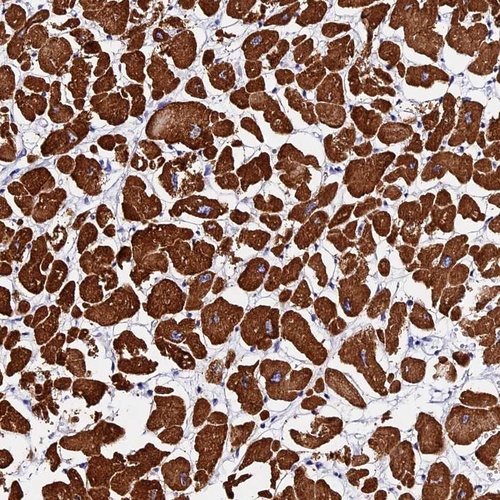

Immunohistochemical staining of human heart muscle shows strong cytoplasmic positivity in myocytes.